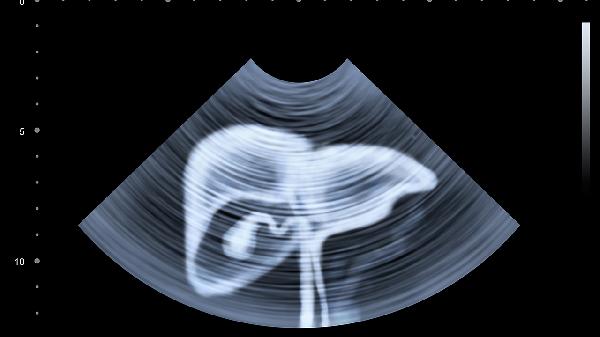

5、定期复查是监测治疗效果和预防复发的重要措施。患者应遵医嘱进行肝功能、病毒载量、肝脏超声等检查,及时发现病情变化,调整治疗方案。